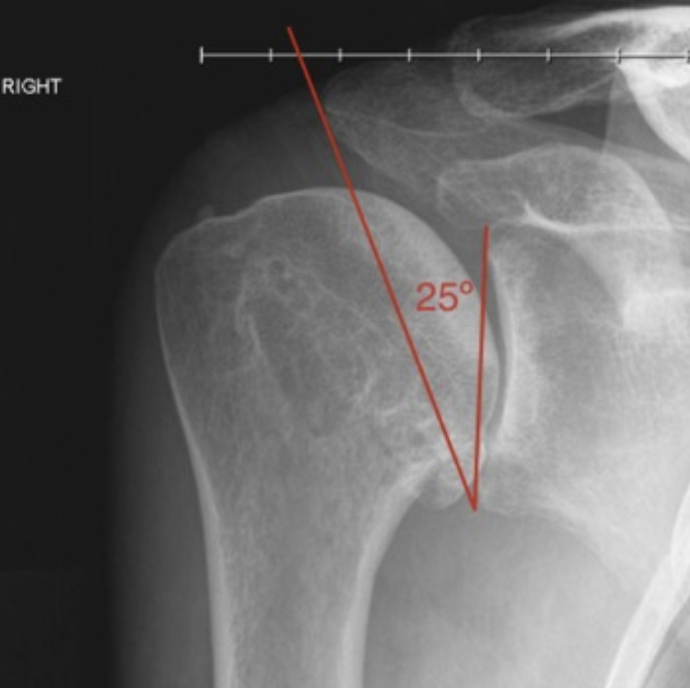

Scapular morphology is also associated with glenohumeral joint arthritis. These include the lateral extension of the acromion as well as glenoid inclination. These two measurements have been combined to give the critical shoulder angle (CSA). Normal values were between 30° and 35°. Both a shorter acromion and a greater inferior glenoid inclination (leading to a lower CSA) result in compressive forces by the deltoid muscle. Values of <30° being implicated in medially directed compressive force across the glenohumeral joint and may lead to excess loading and subsequent OA.20

The critical shoulder angle of <30° being implicated in shoulder OA.26